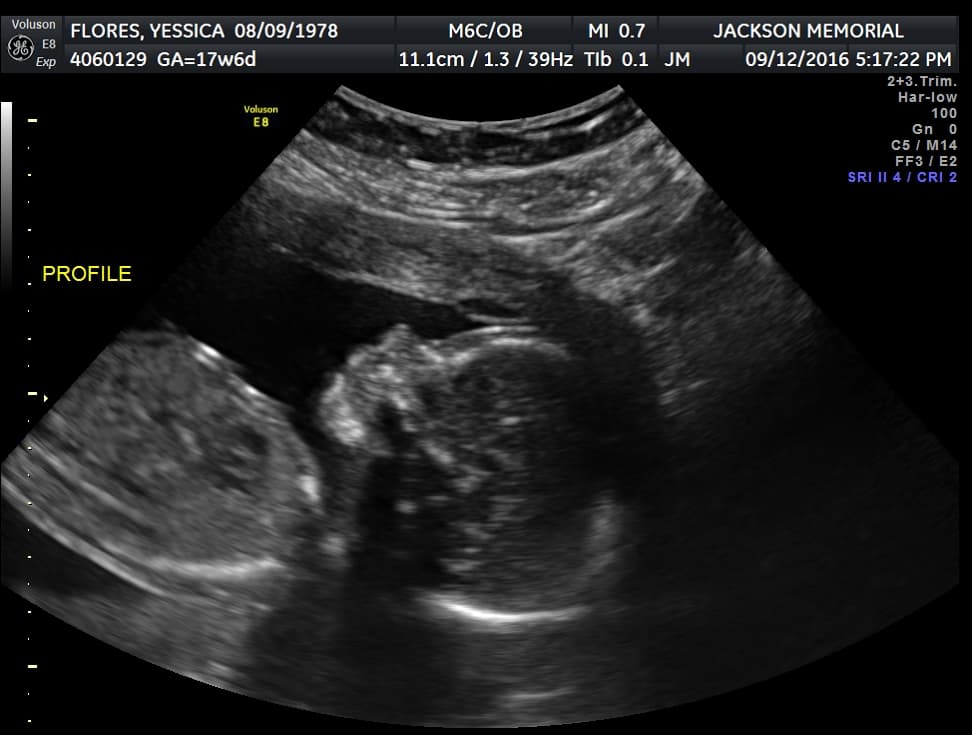

En la actualidad no existe vacuna ni tratamiento para el zika. La única diferencia entre la atención a Flores y a otras embarazadas es que a ella le realizan la prueba del zika cada semana y tiene ultrasonidos más frecuentemente, cada tres semanas.

Christine Curry, su ginecóloga obstetra, dice que hasta ahora todo indica que la bebé está sana y que se desarrolla normalmente. "Estamos fijándonos en el tamaño del cerebro del bebé y de su cabeza. Buscamos calcificaciones, crecimiento anormal de las estructuras intracraneales, niveles de líquido inusual, entre otras cosas", mencionó.

Flores es optimista. "He visto muchos casos de zika donde la mayoría de las madres deciden no tener el bebé para que el bebé no sufra y quiero que tengan fe en Dios y en los médicos", dice, mientras ve las fotos de sus numerosos ecosonogramas.